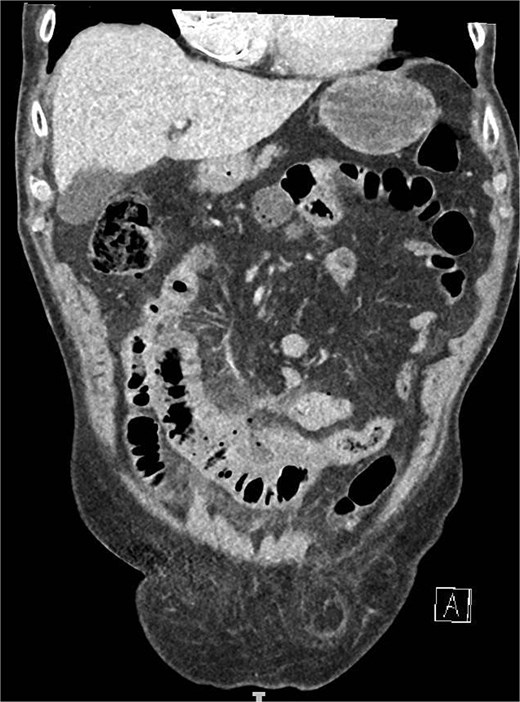

Intraoperatively, a purulent peritonitis was observed, along with an inflammatory, fibrin-covered conglomerate of the small bowel in the lower abdomen. After adhesiolysis, a segment of the distal jejunum ⁓30 cm in length, exhibiting significant inflammatory changes, was identified, with surrounding markedly edematous and thickened mesentery, as well as a diverticulum on the mesenteric wall with suspected perforation into the mesentery. Additionally, multiple non inflamed diverticula, measuring up to 1.5 cm in diameter, were identified along the jejunum. A segmental resection of the inflamed small bowel was performed, followed by a side-to-side anastomosis. The specimen was opened anti-mesenterically in the operating room, allowing for macroscopic verification of the diverticular perforation from an intraluminal perspective (Fig. 2).

Cut open small bowel segment verifying the diverticular perforation (arrow) from an intraluminal perspective.